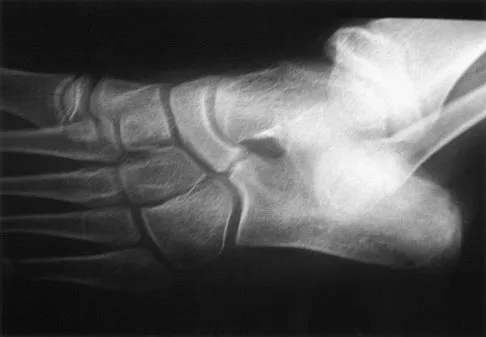

A 28-year-old man has had a 2-year history of progressive lateral ankle pain. History reveals that he underwent a triple arthrodesis at age 13 for a tarsal coalition. The pain has been refractory to braces, custom inserts, and nonsteroidal anti-inflammatory drugs. Weight-bearing radiographs of the ankle and foot are shown in Figures 3a through 3d. Surgical management should include which of the following?

Explanation